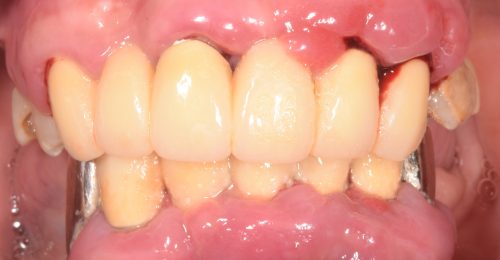

• オールオン4(上顎5本下顎4本)

術前

術後

年齢・性別 63歳・男性

治療期間 5ヶ月、通院回数18回

治療費用 5,720,880円(税込)

治療内容 歯周病により歯が動揺し噛めない状態。仕事に差し支えないように話しやすく、口元も綺麗にしたい。しっかり噛めるようにしたい。